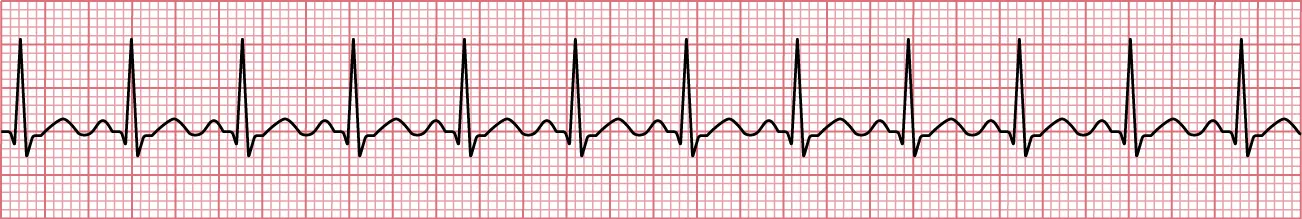

The most common rhythm disturbances occur in the atrial tissue. A popular umbrella term utilized to discuss rhythm disturbances that occur above the ventricles is supraventricular tachycardia (SVT) (Figure 12.14). The most common forms of SVT are atrial fibrillation (AFib) and atrial flutter. AFib is an irregular, fast rhythm originating from the atria due to multiple impulses being fired. The CDC (2022) predicts that by 2030, 12.1 million people in the United States will have AFib. The telemetry qualifiers are regularly irregular, the PR interval is indeterminate due to the irregularity, and the QRS interval is less than 0.12 seconds. AFib is considered rate controlled if the rate is between 60 and 100 bpm, or rapid when rates consistently climb over 100 bpm.

Sinus rhythm showing P waves difficult to distinguish.

Figure 12.14 With supraventricular tachycardia (SVT), the P waves are difficult to distinguish, and without P waves, the PR interval is nonexistent. (attribution: Copyright Rice University, OpenStax, under CC BY 4.0 license)